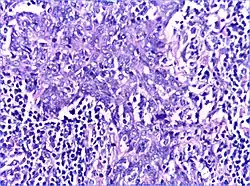

Benign lymphoepithelial lesion or Mikulicz' disease is a type of benign enlargement of the parotid and/or lacrimal glands. This pathologic state is sometimes, but not always, associated with Sjögren's syndrome.